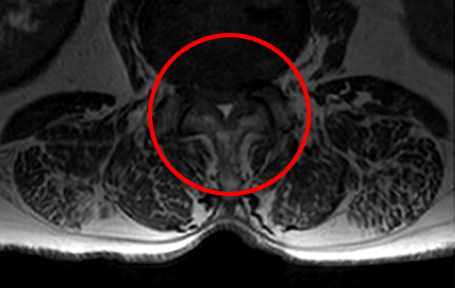

(척추관의 공간이 거의 막혀 있는 상태로,

신경을 압박하여 정상적인 보행이 어려워짐)